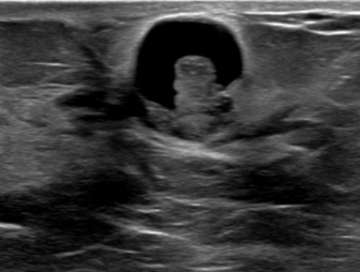

Retraction: Any focal invagination of the skin (often noted as nipple inversion or skin dimpling on physical exam) should be noted, because, like with architectural distortion, this may suggest deeper pathology. Below is an ultrasound demonstrating nipple retraction with an underlying heterogeneous mass with irregular contours. This lesion was highly suspicious (BIRADS 5) and proven to be invasive ductal carcinoma on biopsy.